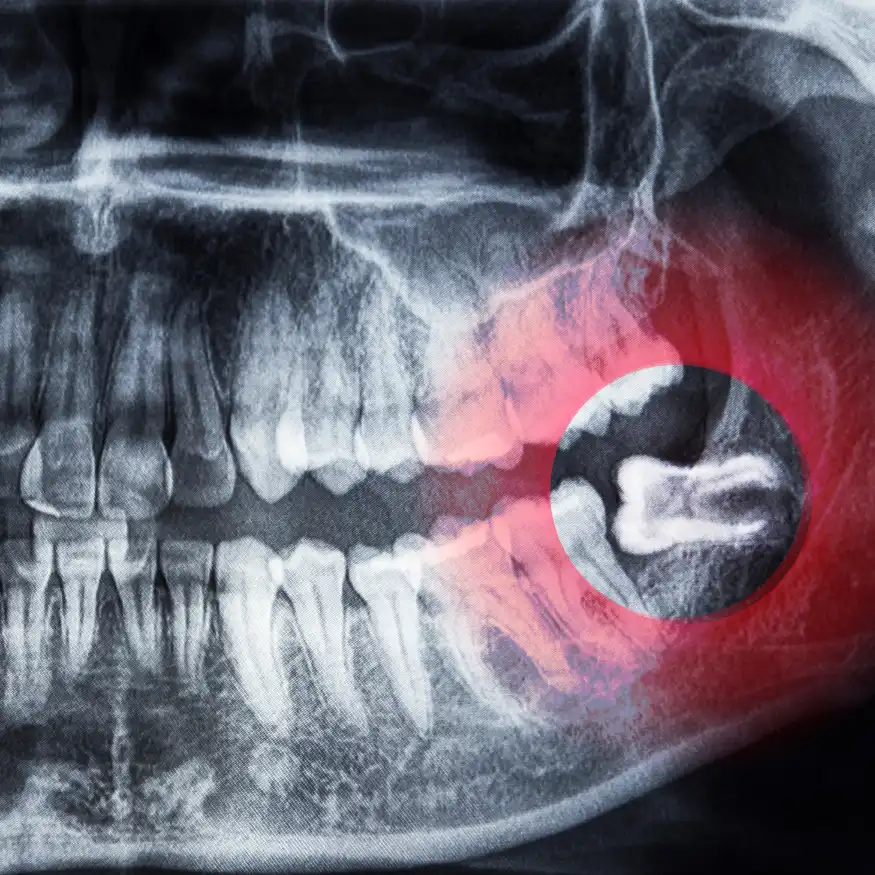

Cirugía Oral - Exodoncia de Cordales

La exodoncia de cordales o muelas del juicio es la extracción de estos molares, que suelen causar problemas por falta de espacio en la mandíbula, causando dolor, infección o incluso desplazamiento de otros dientes.

Beneficios

Retirar las muelas del juicio previene problemas de alineación dental, infecciones, dolor y daños en los dientes adyacentes. También facilita la higiene bucal, ya que estas muelas pueden ser difíciles de limpiar.

Proceso

Antes de la cirugía, se realiza una evaluación radiográfica para planificar la extracción. Luego, bajo anestesia, se realiza la extracción quirúrgica, y se brindan instrucciones detalladas para el cuidado postoperatorio que incluye manejo del dolor y recomendaciones para una recuperación rápida y sin complicaciones.